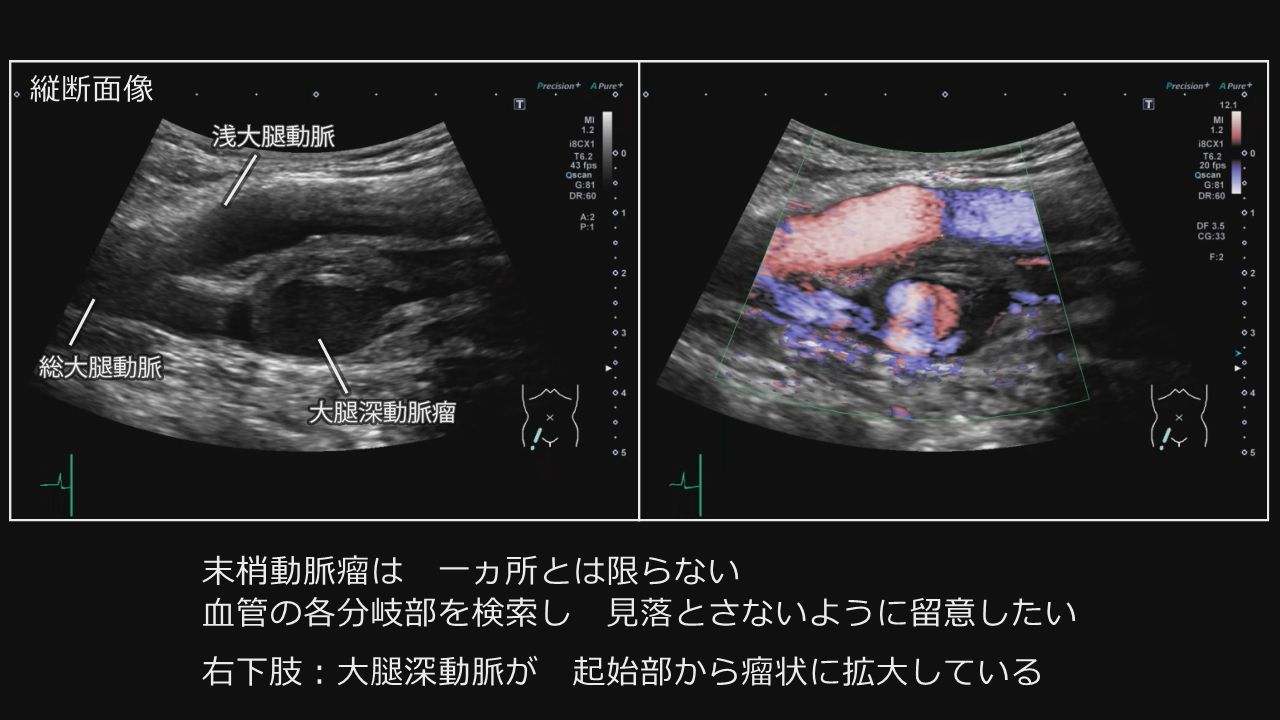

PowerPoint プレゼンテーション。

大動脈、腹部・下肢動脈エコーの攻略法動画ライブラリ。